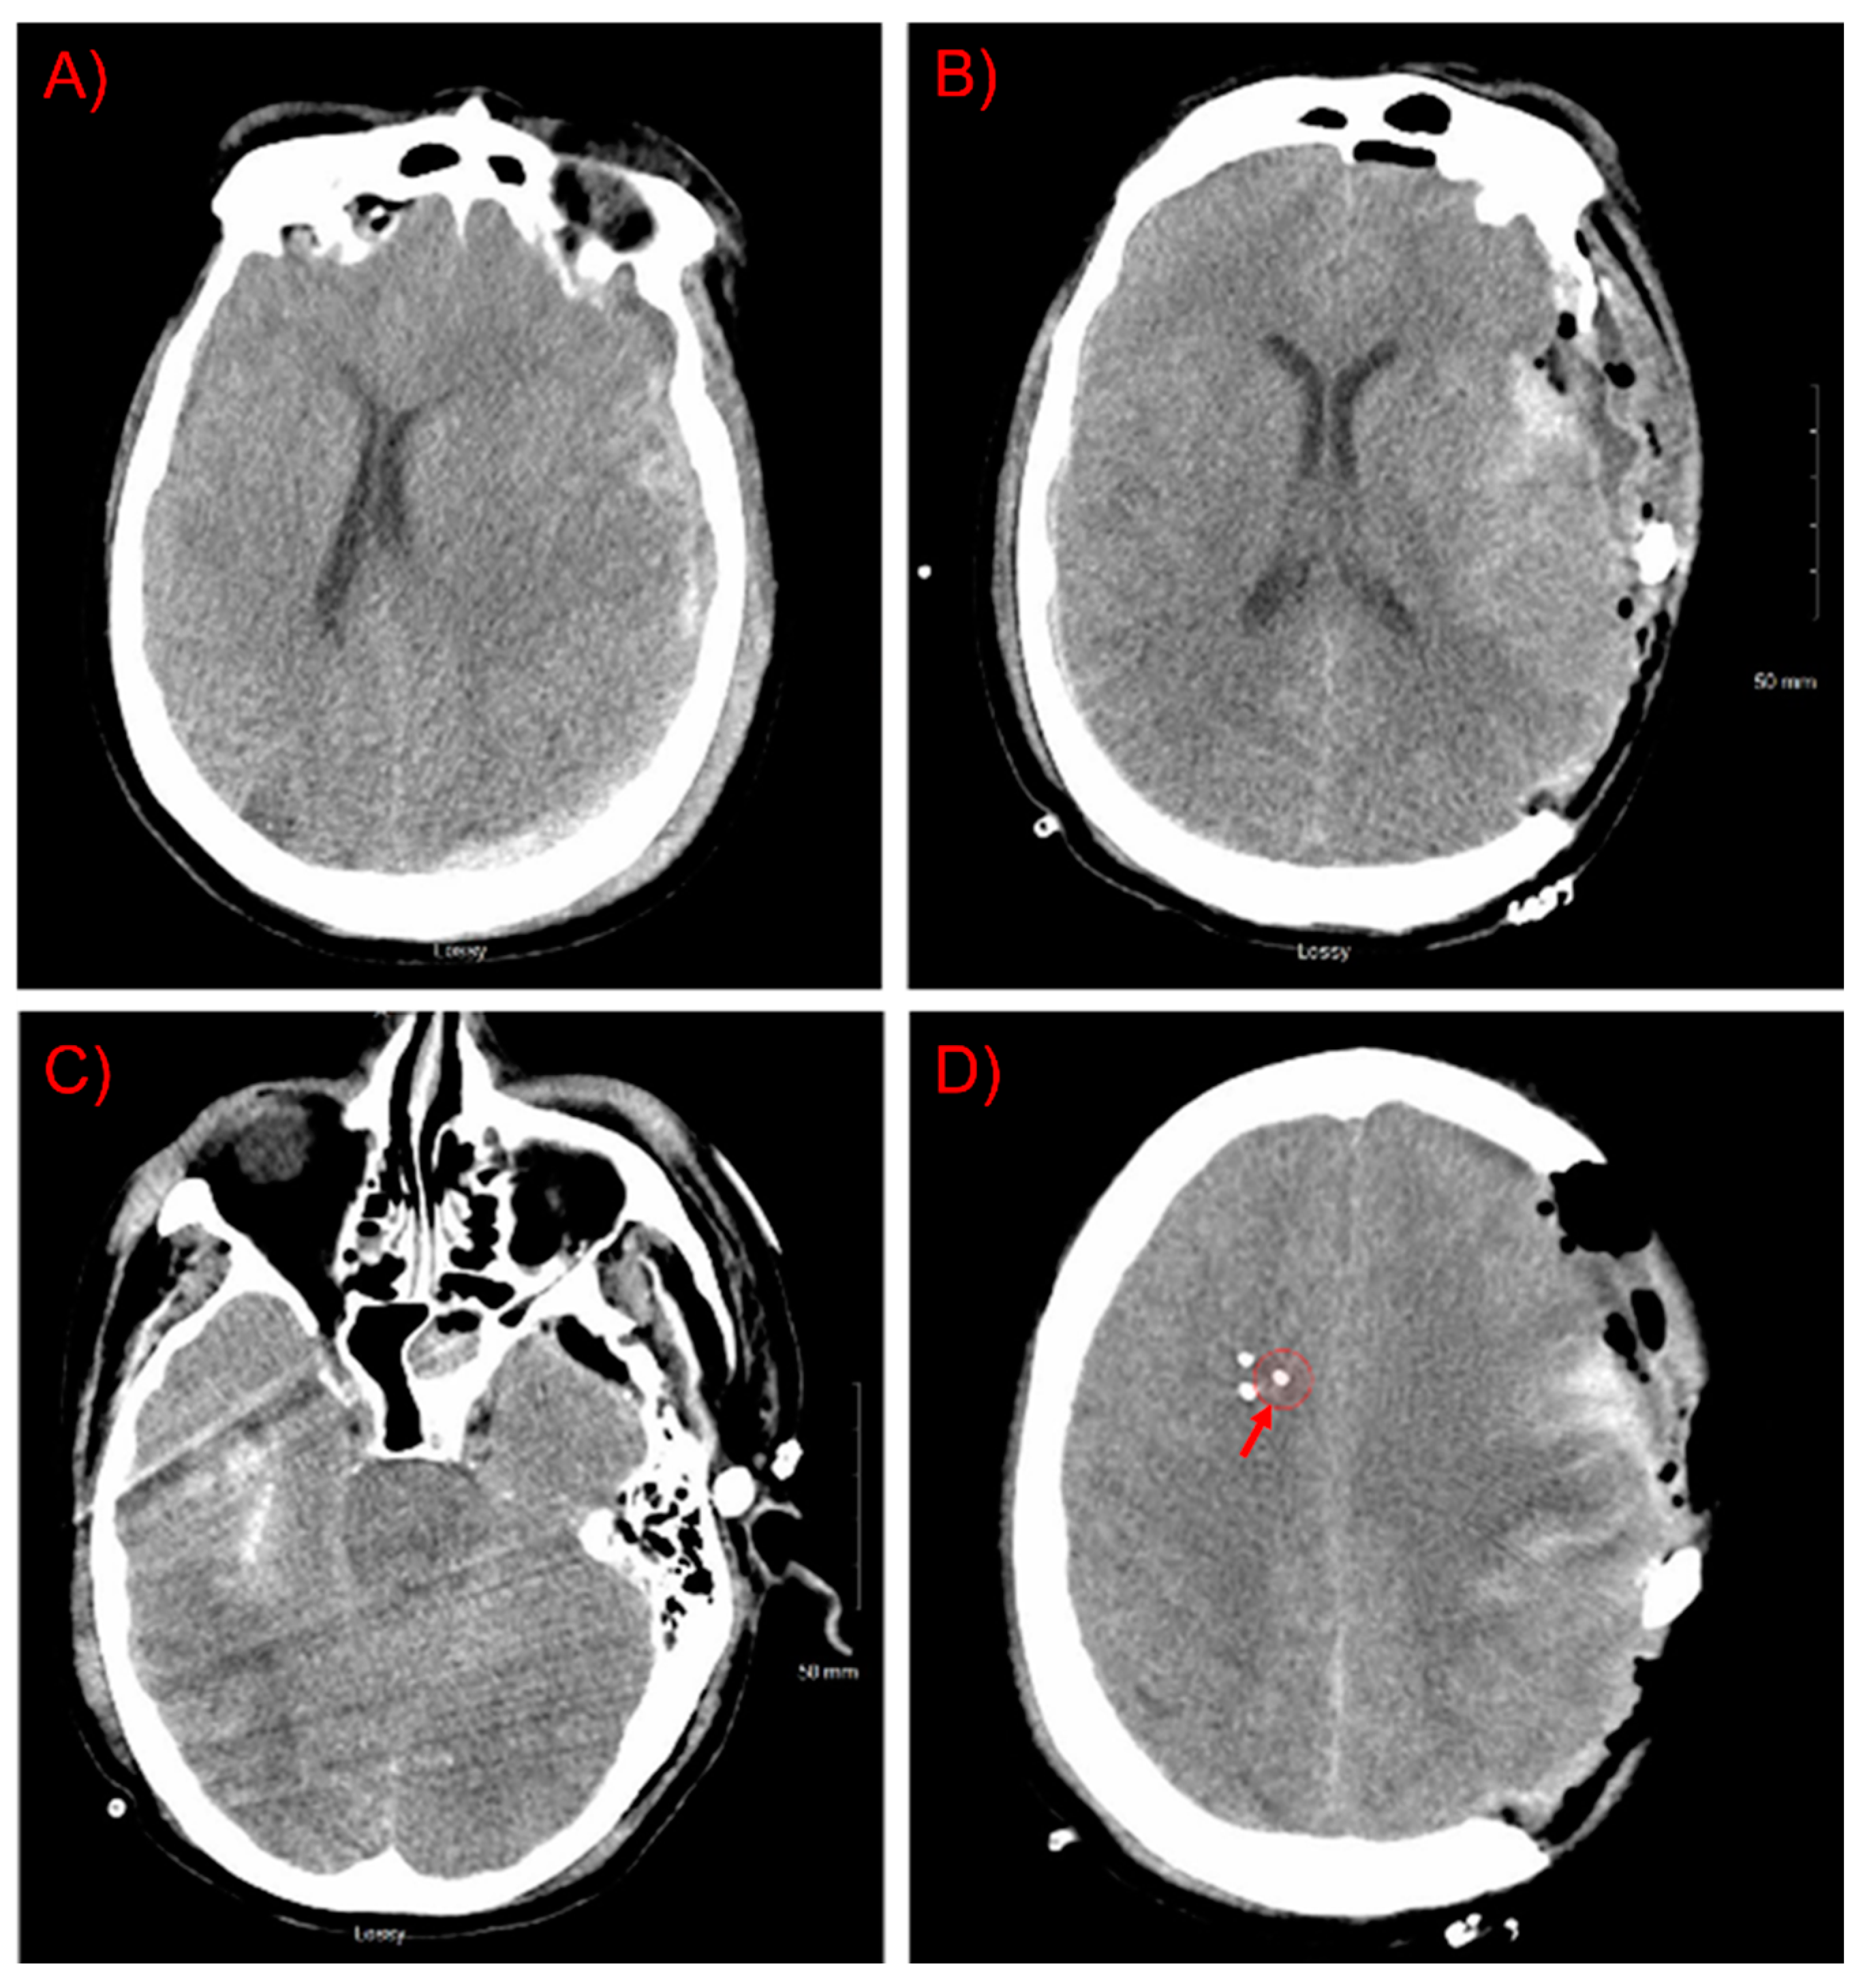

2.1. Study Design and Patient Details